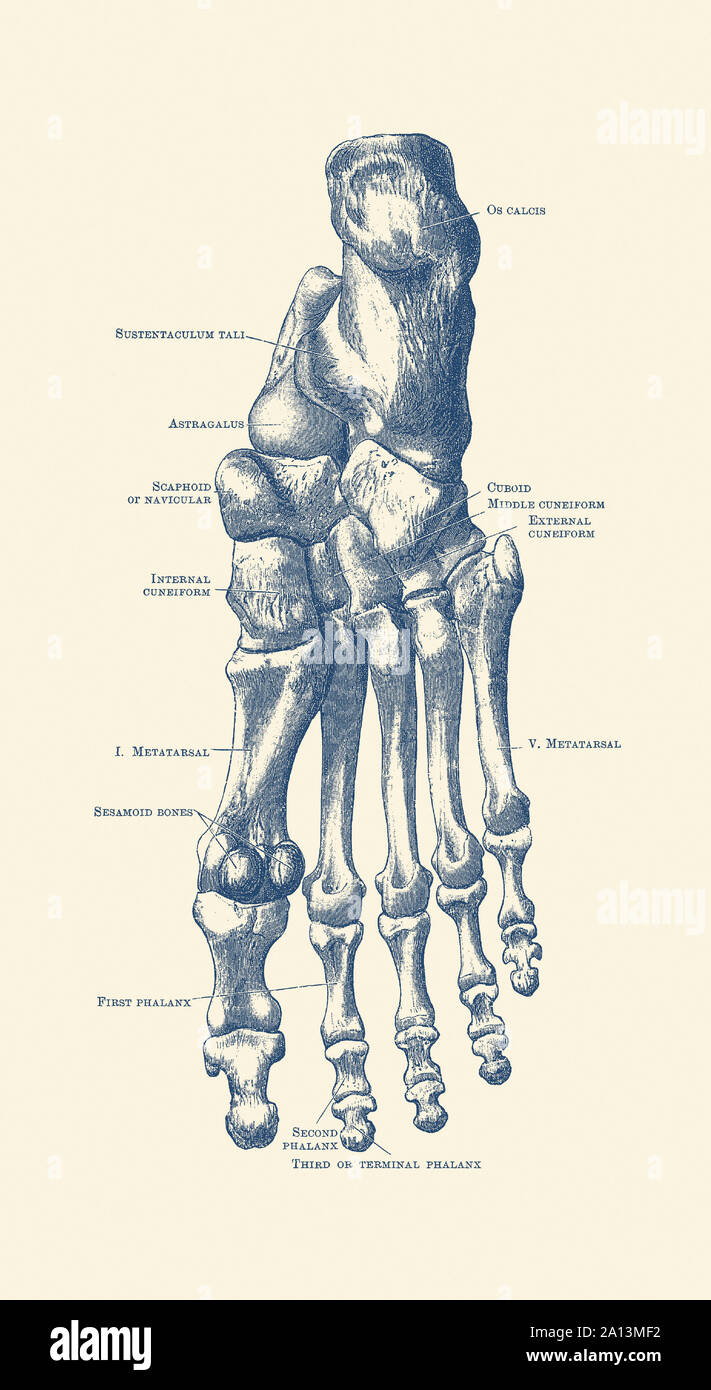

RF2DHMD0H–OS du pied. Anatomie humaine. Le schéma montre l'emplacement et le nom de tous les os du pied.

RM2A83MWT–Opinions de l'os dans le pied humain, de la cheville aux pieds. La gravure sur cuivre par Edward Mitchell après une illustration anatomique par Jean-Joseph Sue de John Barclay's une série de gravures du squelette humain, MacLachlan et Stewart, Édimbourg, 1824.

RMK228DY–Partie terminale du membre inférieur, reposant sur le sol au cours de posture droite ; le squelette du pied a 26 os.

RMK227XM–Partie terminale du membre inférieur, reposant sur le sol au cours de posture droite ; le squelette du pied a 26 os.